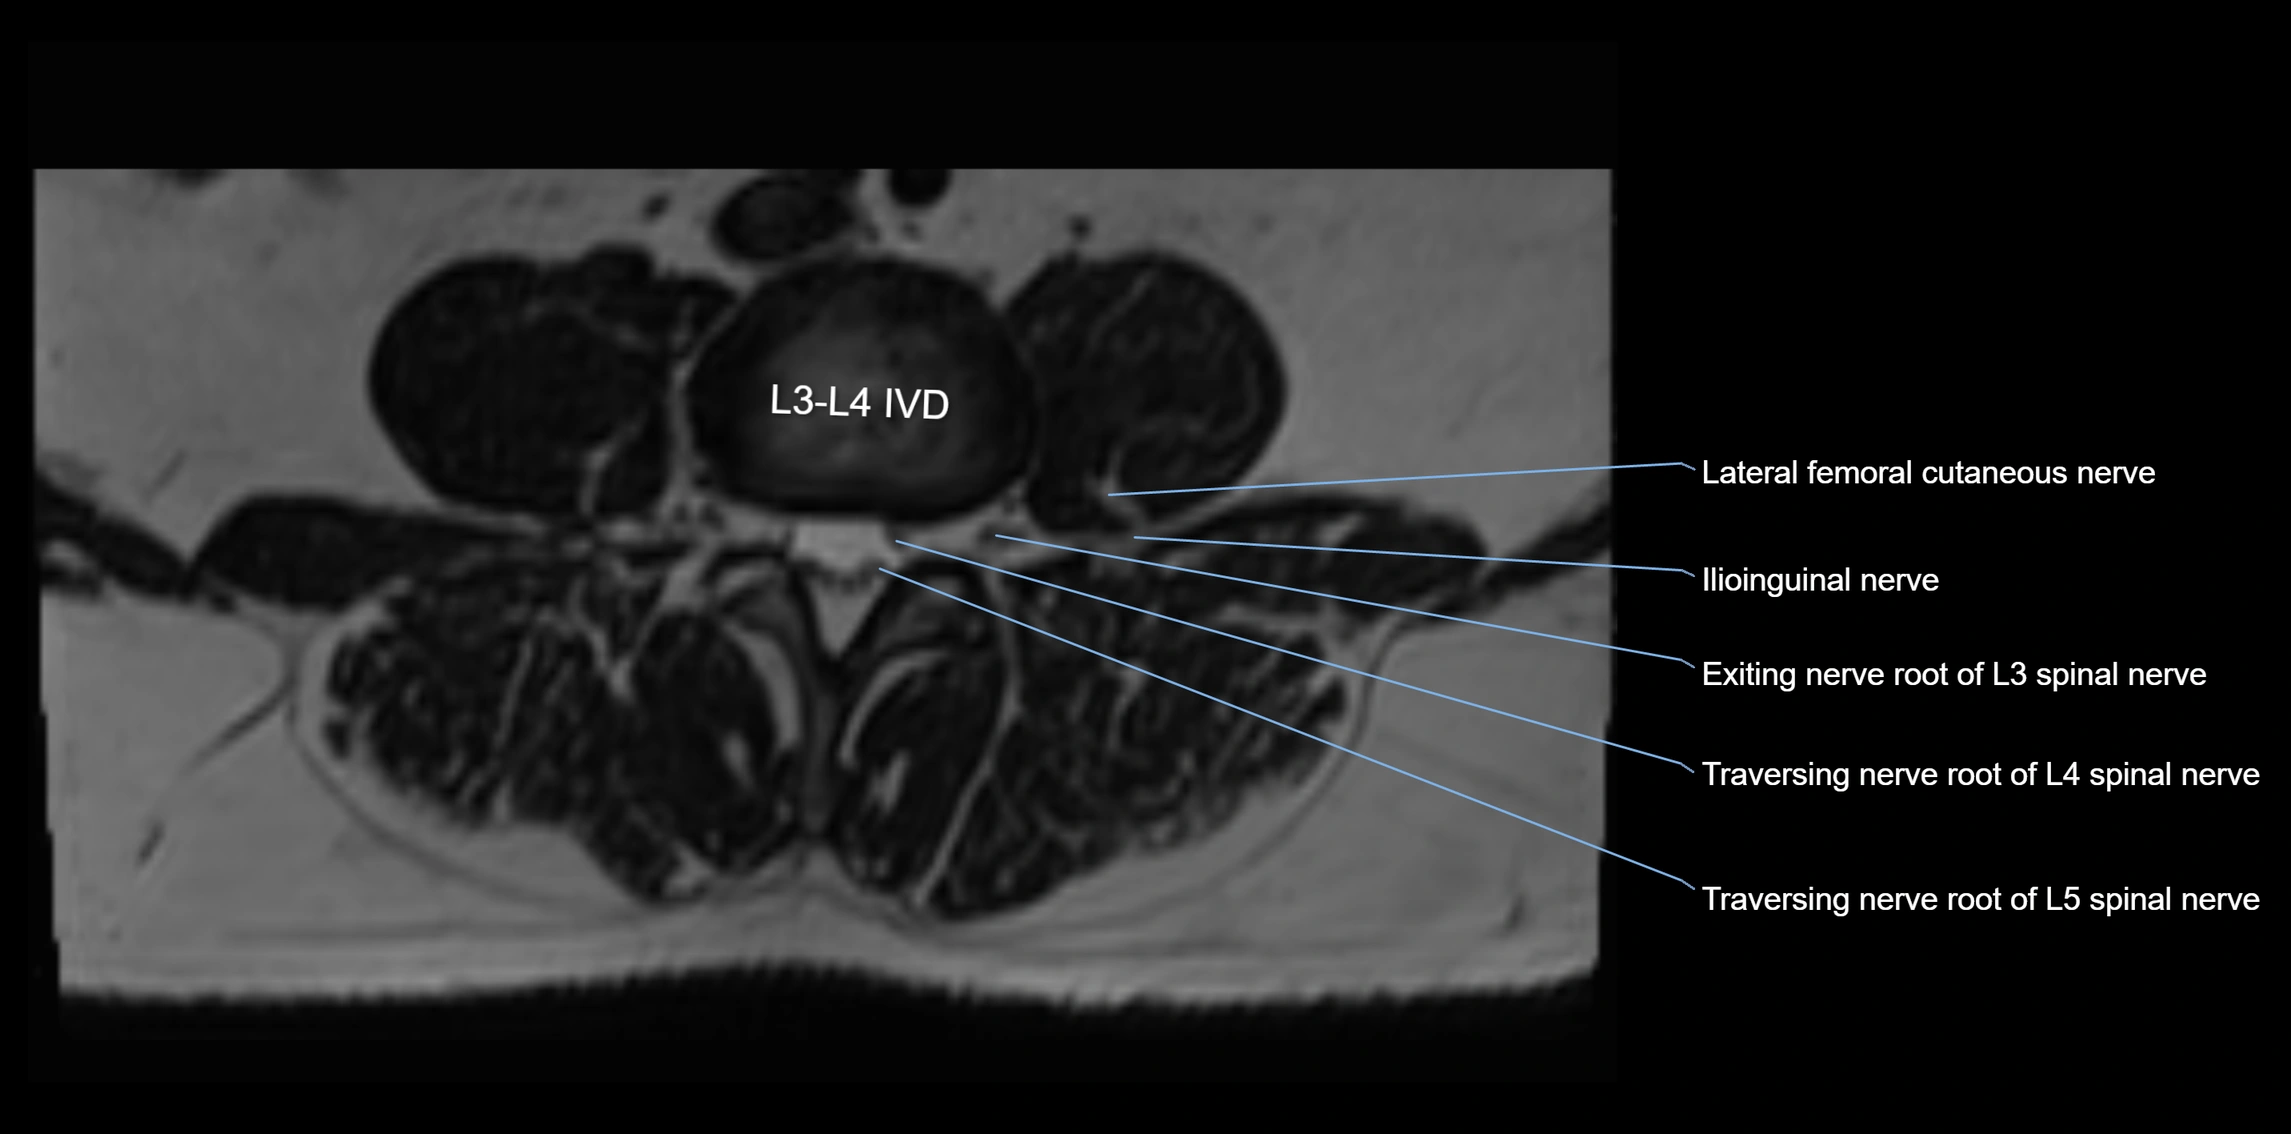

MRI image

image